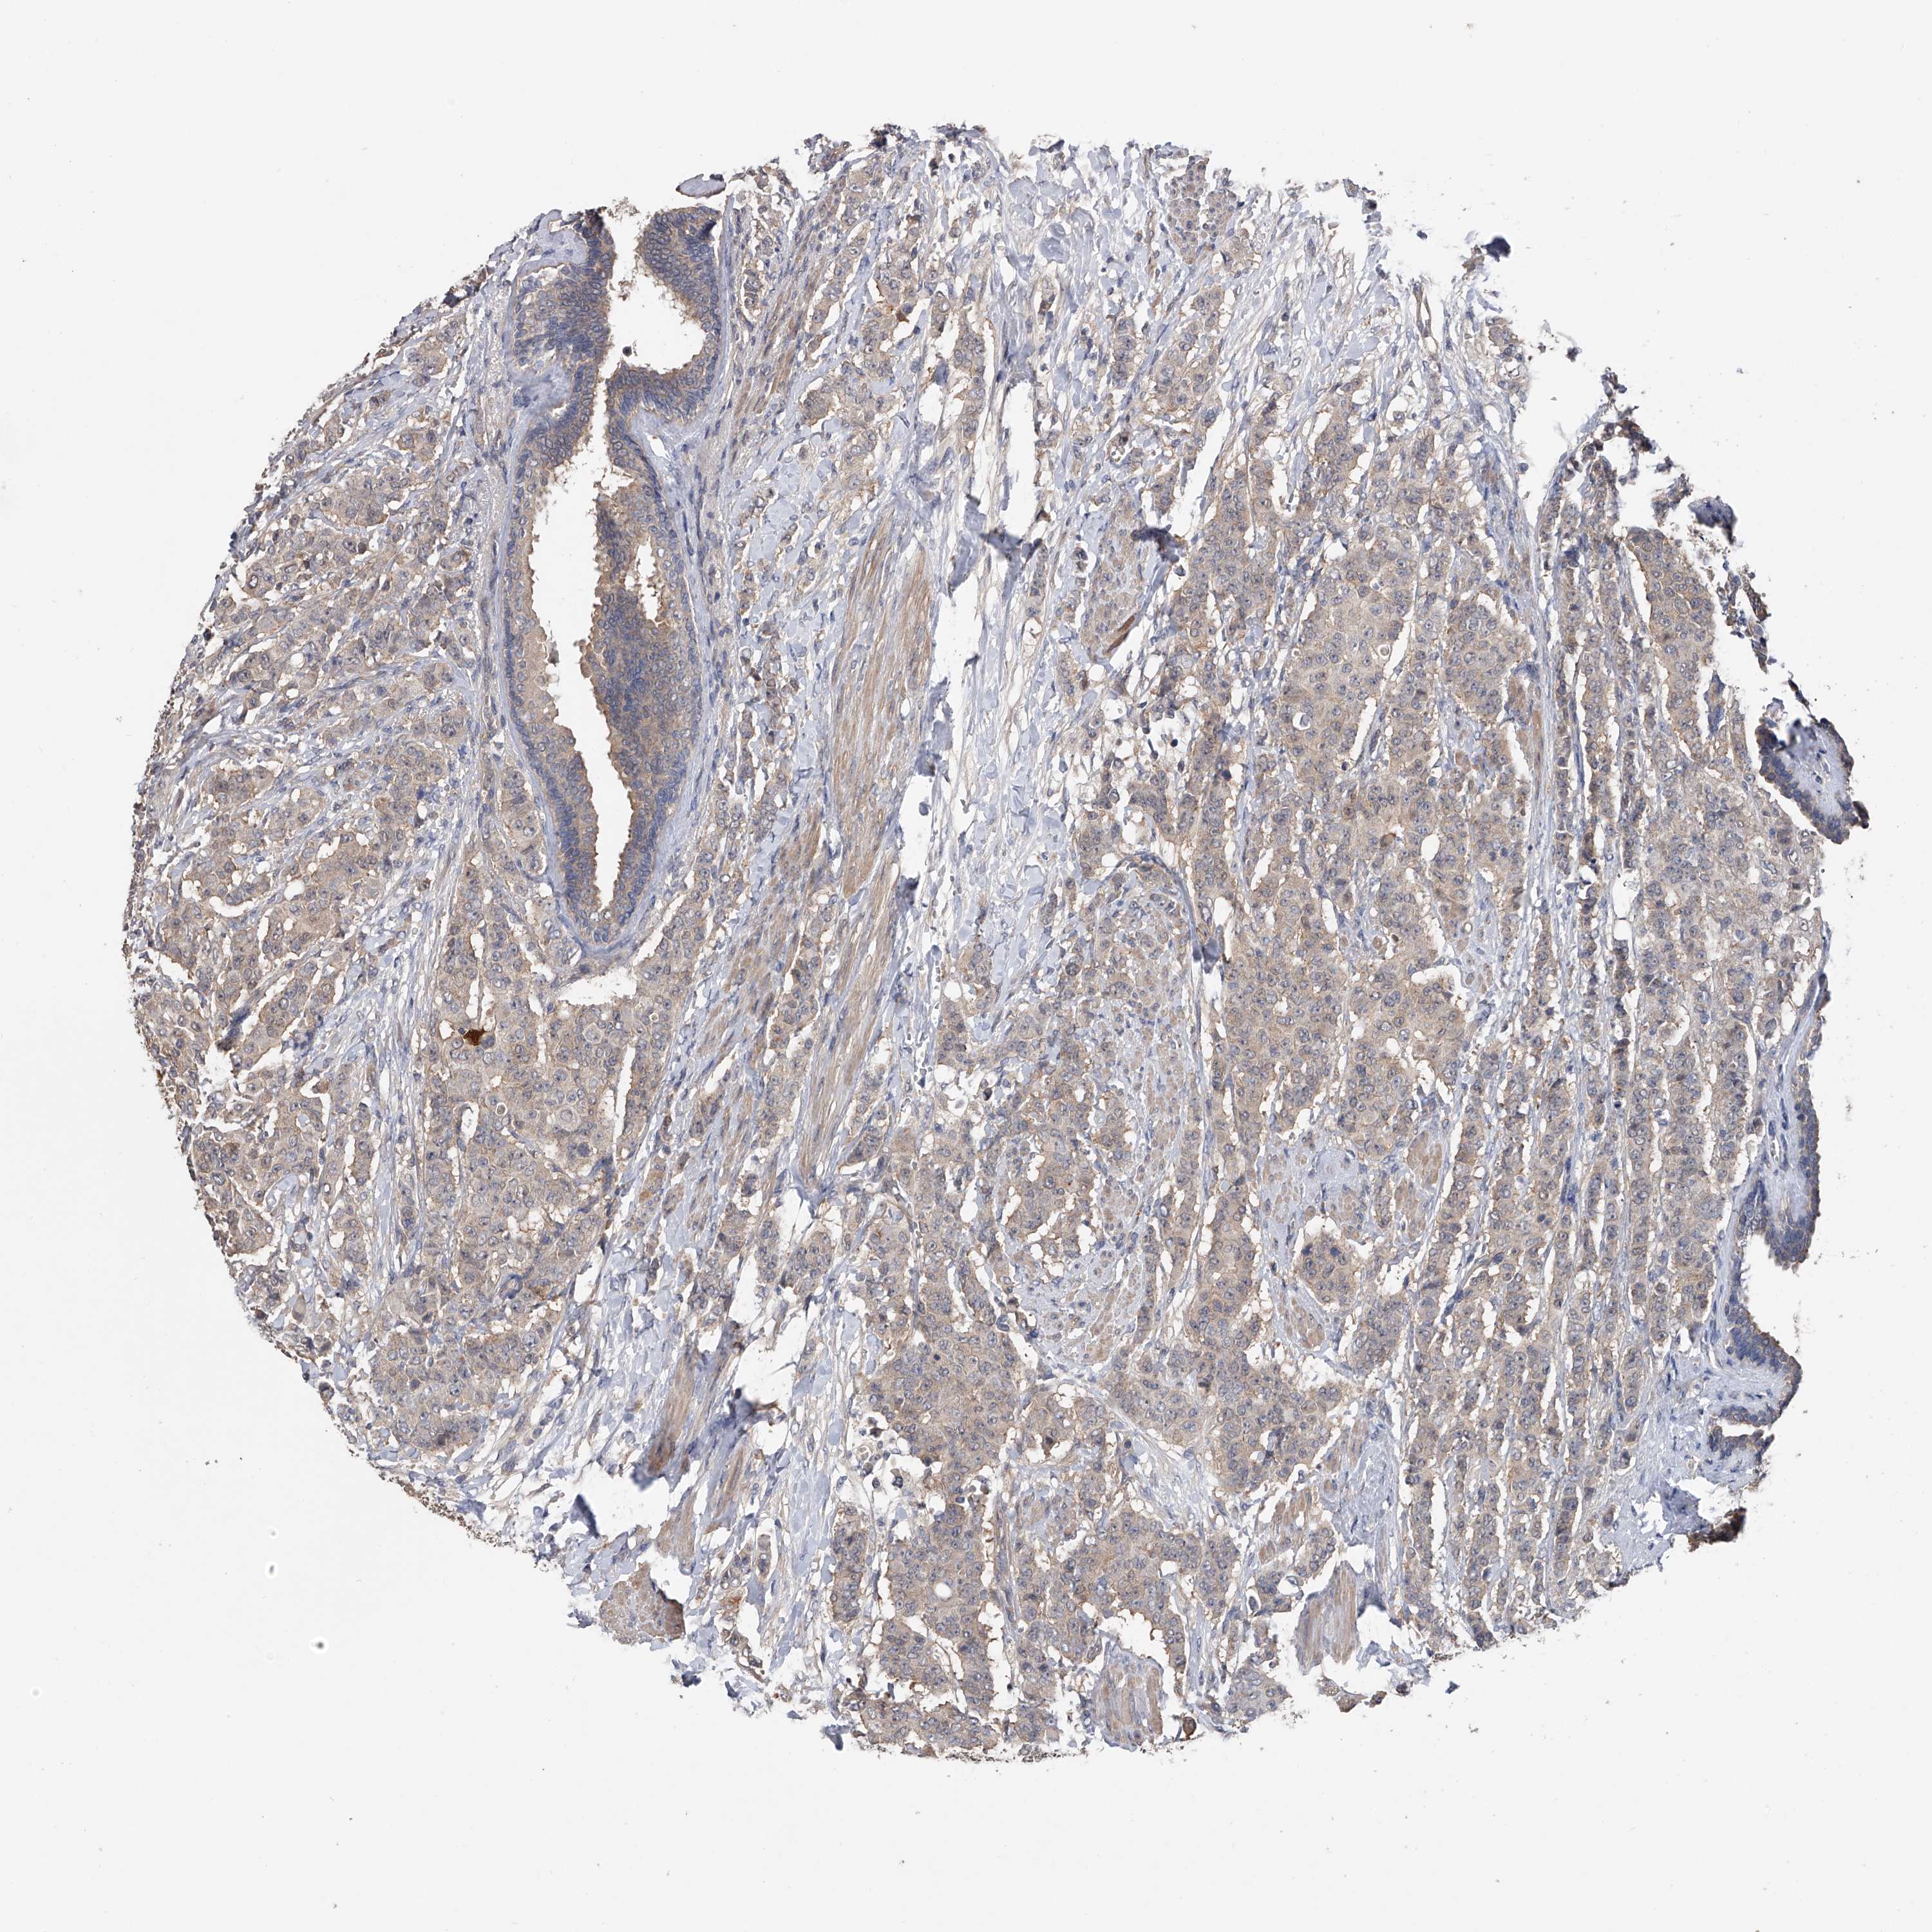

BRCA TCGA BRCA VALIDATION PROTEIN EXPRESSION

ANTIBODIES

AND

VALIDATION